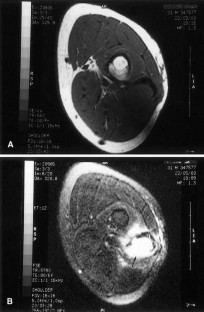

Fig. 1

Fig. 2

Fig. 3